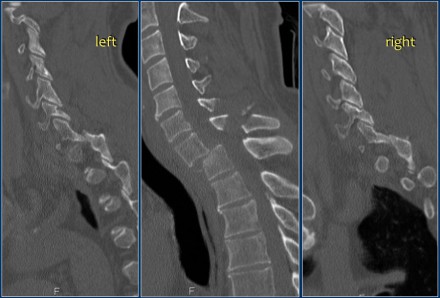

Look at the images.

What are the findings?

Then scroll to the next images.

The findings are:

- Vertebral bodies show marrow edema as a result of a fracture.

- Torn flaval ligament (yellow arrow).

- Fractures through the posterior elements (red arrows).

The TLICS-score is high, because there is distraction and injury to the PLC.